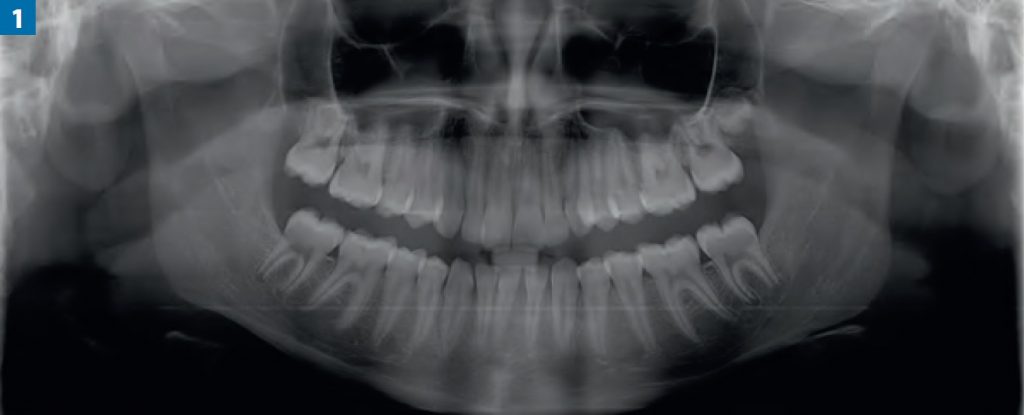

Streszczenie: W artykule przedstawiono współczesną wiedzę na temat zaburzenia rozwojowego zębów o charakterze zmniejszonej liczby zębów oraz częstość występowania, postacie kliniczne i rodzaje klasyfikacji tego typu zaburzeń. Wrodzony brak zawiązków zębów częściej występuje u dziewcząt niż u chłopców (w proporcji 3:2) i należy do najczęstszych wad rozwojowych uzębienia. Wada ta może występować zarówno jako samodzielna, jak i w połączeniu z wadami rozwojowymi (zaburzenia morfologii, opóźnione ząbkowanie, zmiany położenia zębów). Leczenie interdyscyplinarne, które musimy zastosować w takich przypadkach, jest leczeniem trudnym i musi uwzględniać odpowiednio dobraną diagnostykę radiologiczną.

Summary: The article presents the contemporary knowledge about tooth agenesis, the frequency of its occurrence, its clinical forms, as well as the types of classification of this disorder. The inherent lack of tooth germs is more frequent in girls than boys (3:2) and is among the most common dental developmental disorders. It may occur separately but also together with other developmental disorders (morphological disorders, late teething, change of teeth location). The interdisciplinary treatment which is necessary in such cases is difficult and must take into account proper radiological diagnostics.

Brak zawiązków zębowych jest najczęściej spotykanym zaburzeniem rozwojowym uzębienia (częstość występowania waha [...]